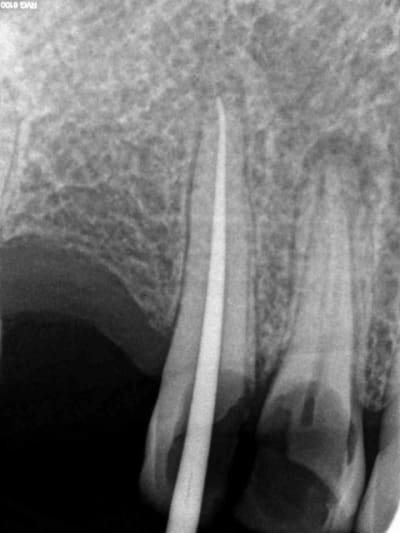

Aujourd'hui patient en urgence ca tombe bien pour une fois synchro avec un lapin.

45 mn de turbinage intensif 2 endos + 2 SC 33; On cote comment les radios ?

Z6, SC 20, Z3,Z3, SC20, Z3, Z3, SC 33, Z3, SC 33, Z3 ?